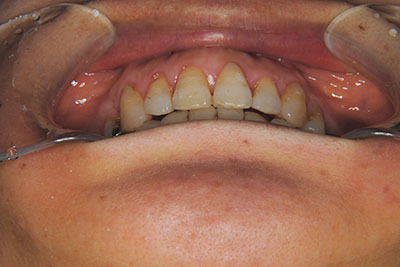

おとなの方でも矯正治療をあきらめないでください!

矯正歯科治療は子供の頃だけしかできない……

子供の頃に比べ大人になったら治療期間がすごく長い……

というようなイメージをお持ちではありませんか?

子供の頃に矯正治療を行う方が治療期間が短く済むというのは、確かですが、矯正治療は患者様の意識も重要です。

いくら歯が動き易くとも、本人がやる気でなければ効果は出ませんし、むし歯発生のリスクも高まります。おとなの方は顎の成長が終わっているため、治療の計画が立てやすいとも言えます。「もう大人だから…」とあきらめず、一度ご相談ください。

本格矯正治療の詳しい説明は小児矯正治療/本格矯正治療ページを御覧ください。